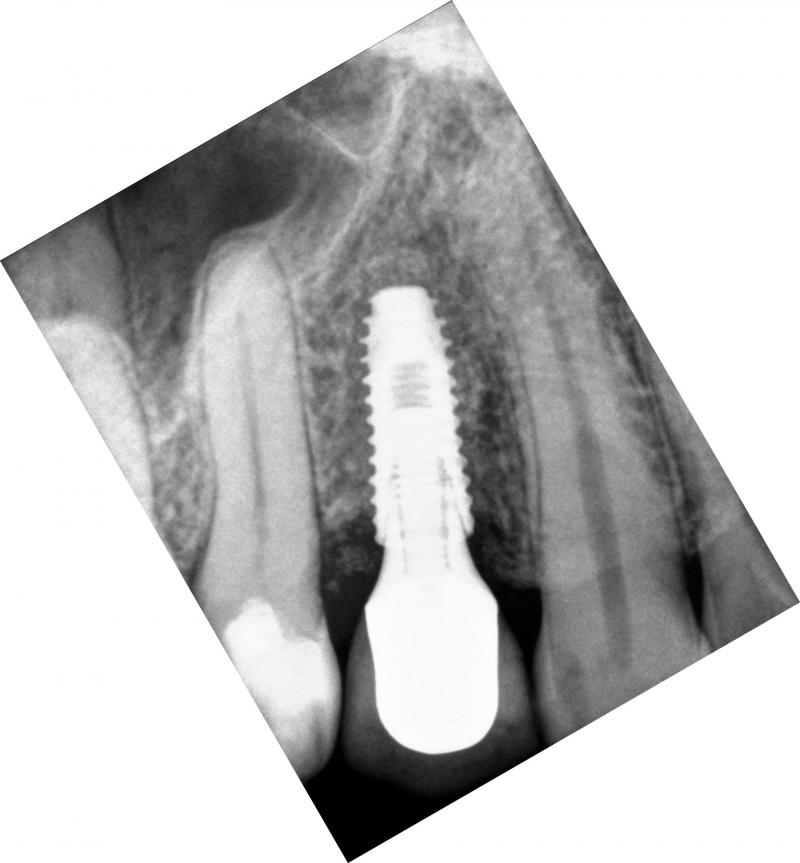

In this case of a single implant, a fully-guided system is used. The implant is perfectly placed center, between the roots of the two natural teeth (Fig. 5). PA means periapival; BW means bitewing. The implant is placed such that its platform is about 0.5-1 mm apical from the alveolar crest.

(a)

(b)

(c)

Fig. 5. A good implant placement: (a) implant and healing abutment (PA view), (b) implant and healing abutment (BW view), and (c) implant, implant abutment, and implant crown (PA view, a month later)